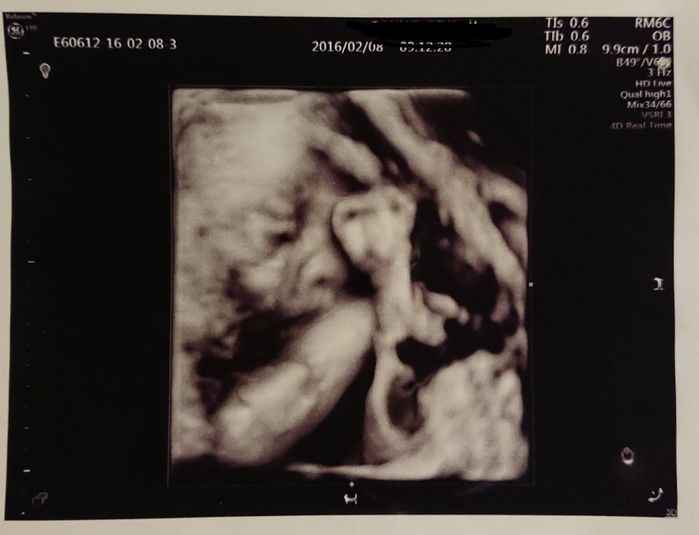

妊娠28週目 エコー写真に全身が入らないくらい大きくなりました

8ヶ月に入り、日に日に大きくなるお腹。胎動も激しくなり夜中に起きることも。仕事中に長時間立っているのがつらくなり、疲れやすくなってきました。赤ちゃんの顔がだいぶはっきりしているのが写真でわかります。